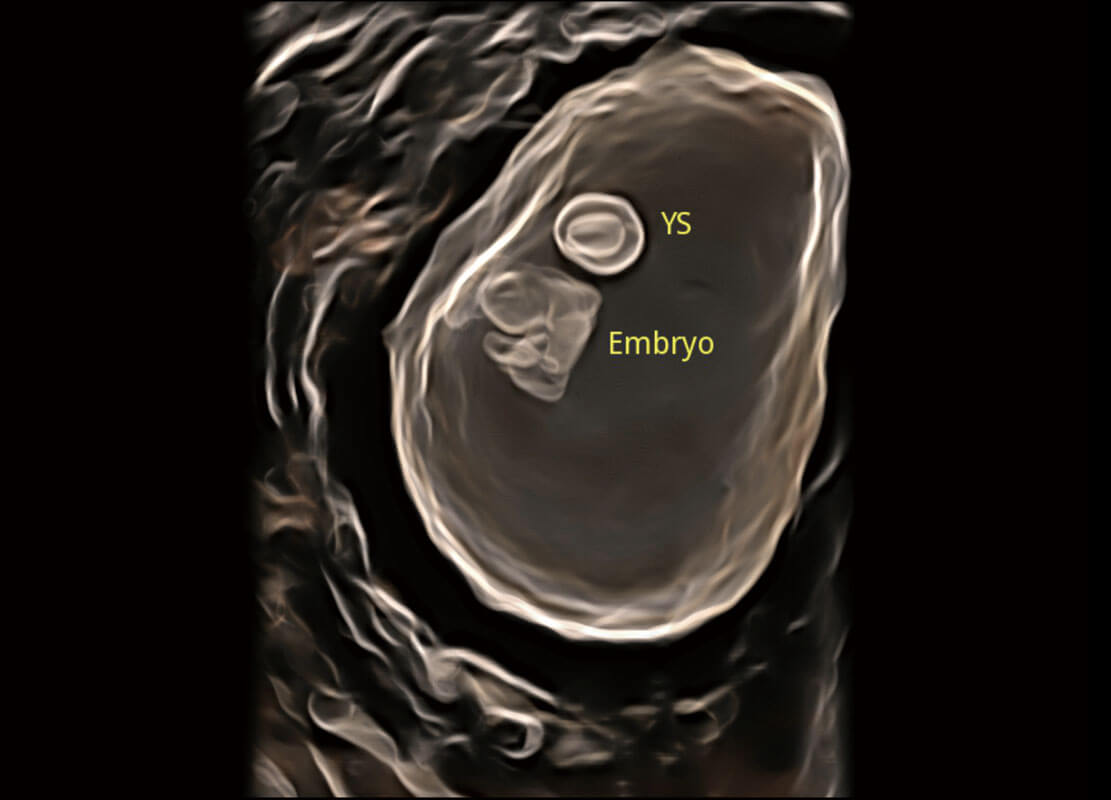

P60在胎儿早孕期超声筛查中为您带来优异的图像质量。

高分辨率容积成像-早孕胎儿

光影成像-孕囊